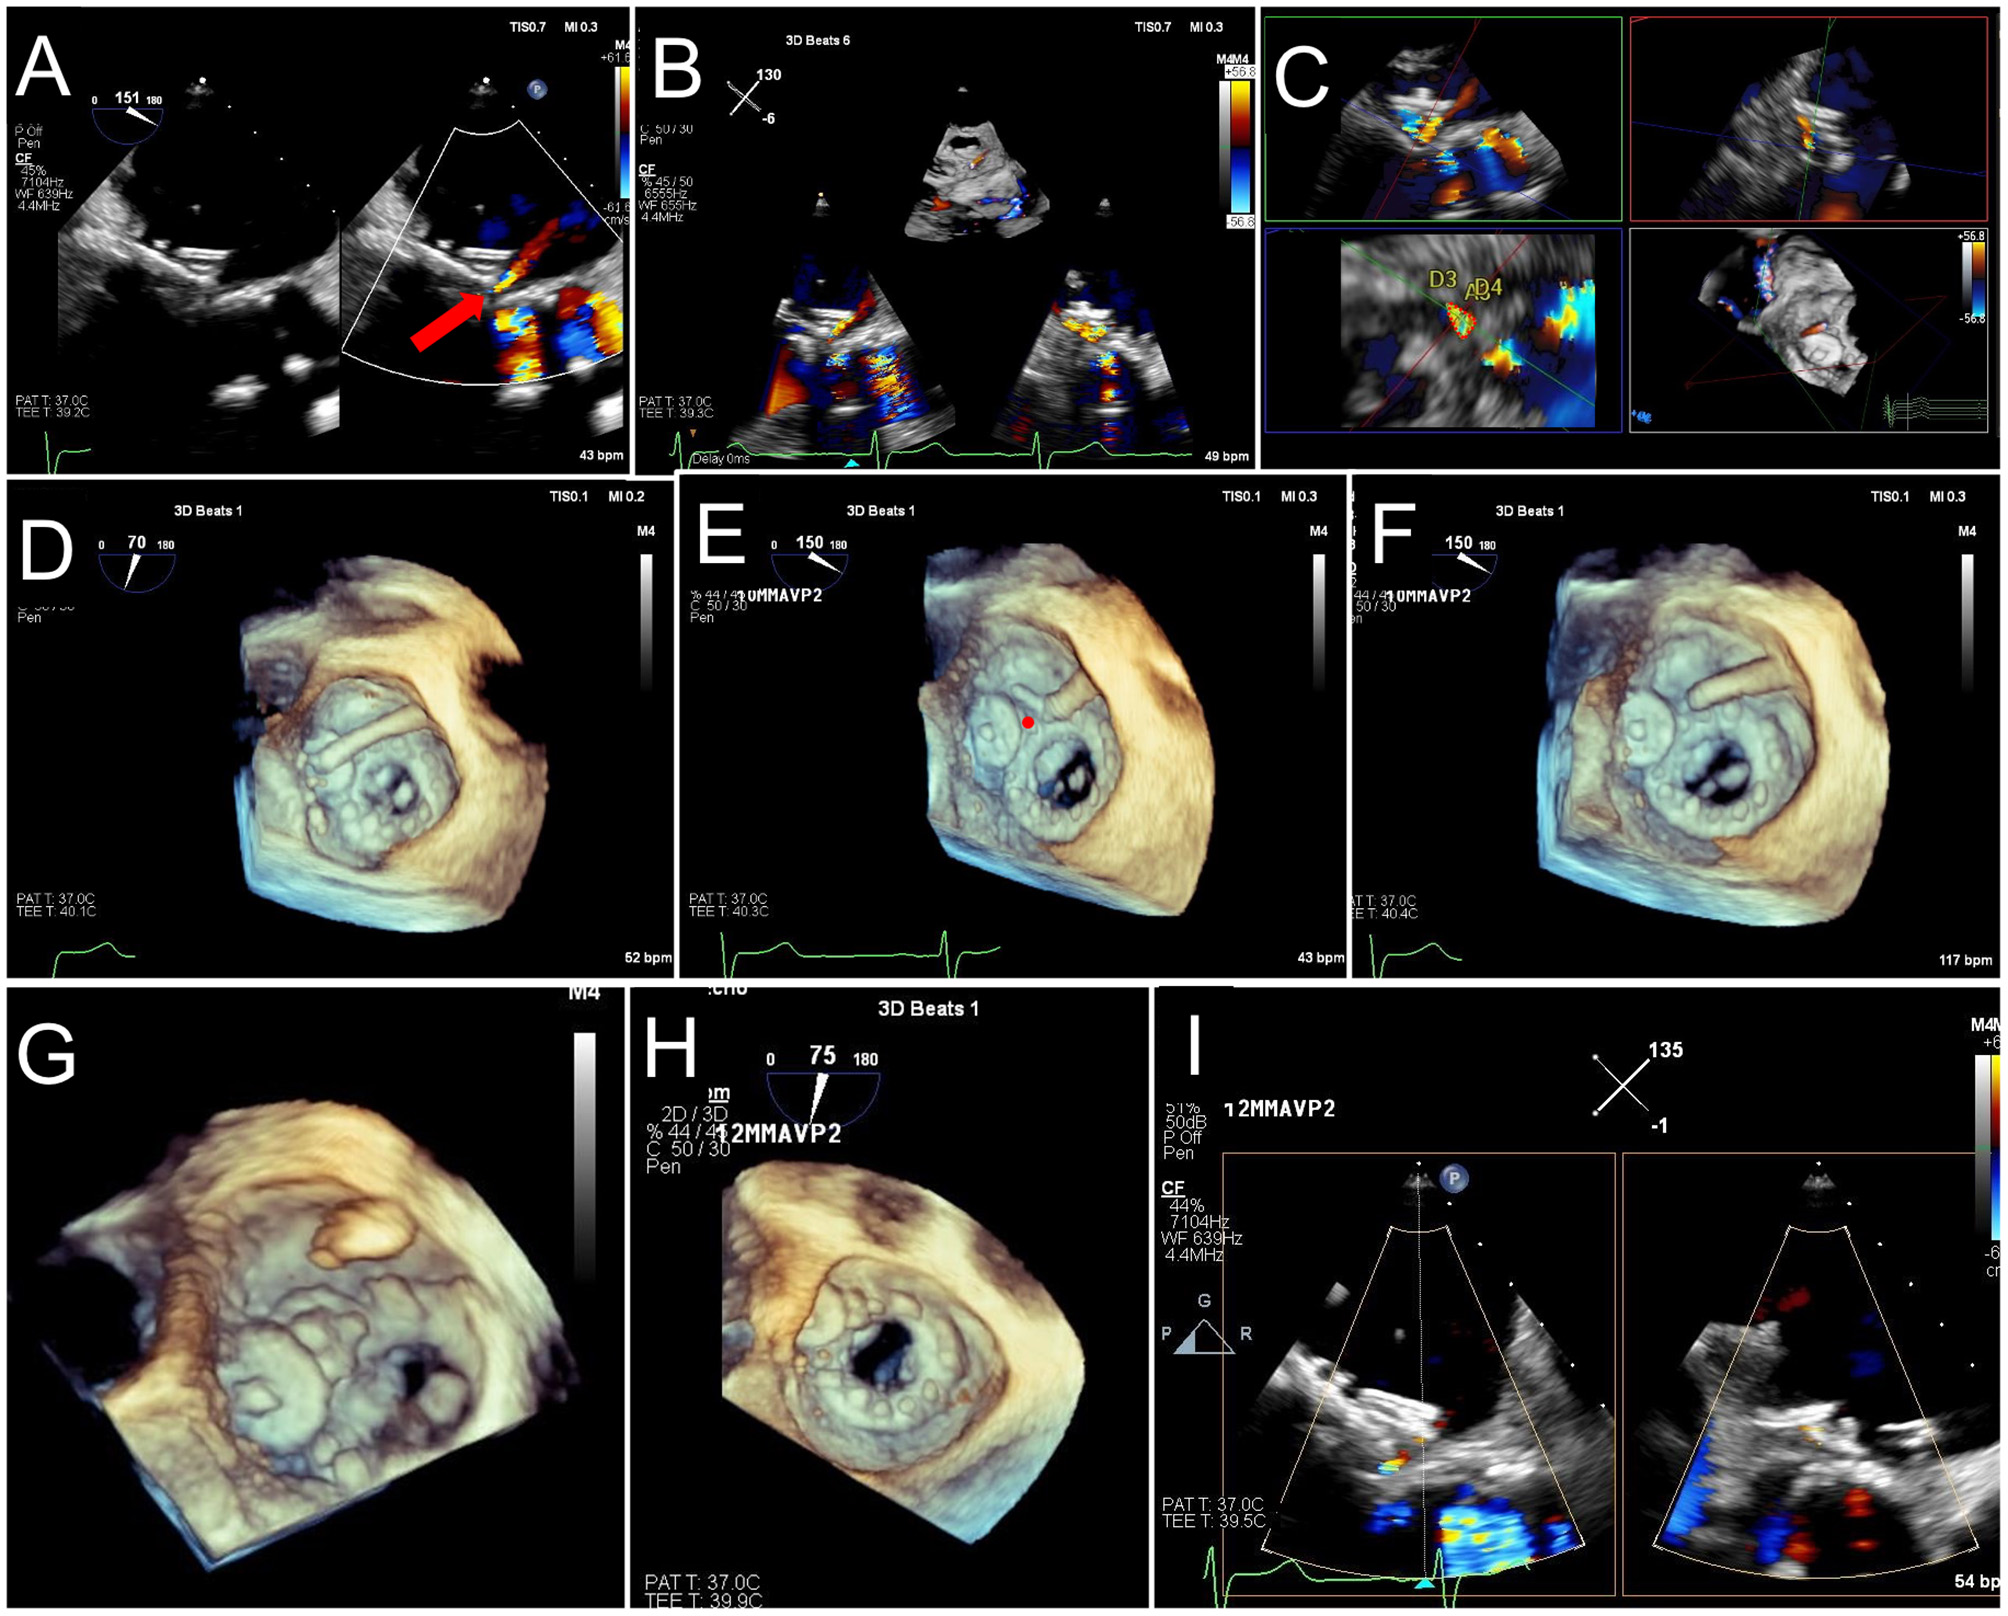

Figure 12

TEE Guided Implantation of a Second PVL Closure Device for Residual Leak. (A) After an initial deployment of a 10 mm AVPII device, a residual leak is seen adjacent to the first device (red arrow). (B) A sector-based 3D Color Doppler acquisition demonstrates the location of the residual leak medial to the first device. (C) Multiplanar reconstruction of the 3D color Doppler acquisition is aligned with the jet for measurement of the paravalvular defect (lower left panel, dotted red tracing), measuring 17 mm2, with dimensions 10 x 4 mm. (D) The guide catheter is positioned on top of the first device, too lateral to enter the defect. (E) The guide is pulled back, and wire crossing of the defect (red circle) is attempted. Wire trajectory is medial and anterior to the defect. (F) After correction of wire trajectory, the defect is crossed. (G) A 12 mm AVPII device is deployed within the residual defect. (H) Bioprosthetic leaflet opening appears normal, without interference from the closure devices. (I) Biplane color Doppler imaging demonstrates trivial residual leak after deployment of the 2nd PVL closure device.